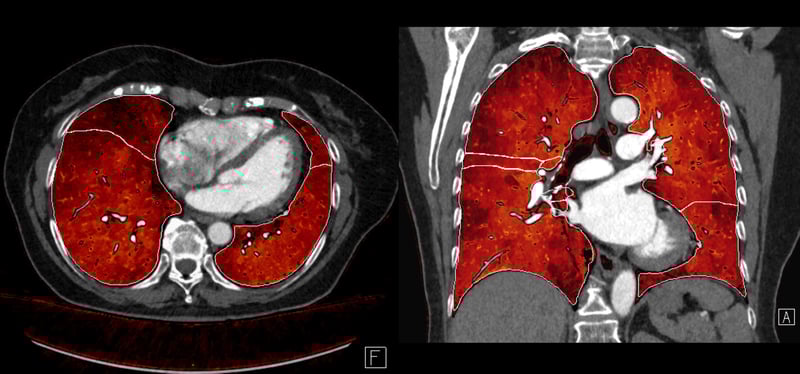

Lung Analysis

Iodine-based perfusion imaging enables functional assessment of the lungs—particularly valuable in cases of pulmonary embolism.

Perfusion Map

Perfusion maps support the detection of small pulmonary emboli that are easily missed in standard reconstructions. Color-coded images highlight perfusion deficits immediately, facilitating fast and intuitive reporting.

Figure 4: Color-coded visualization of pulmonary perfusion in two views.